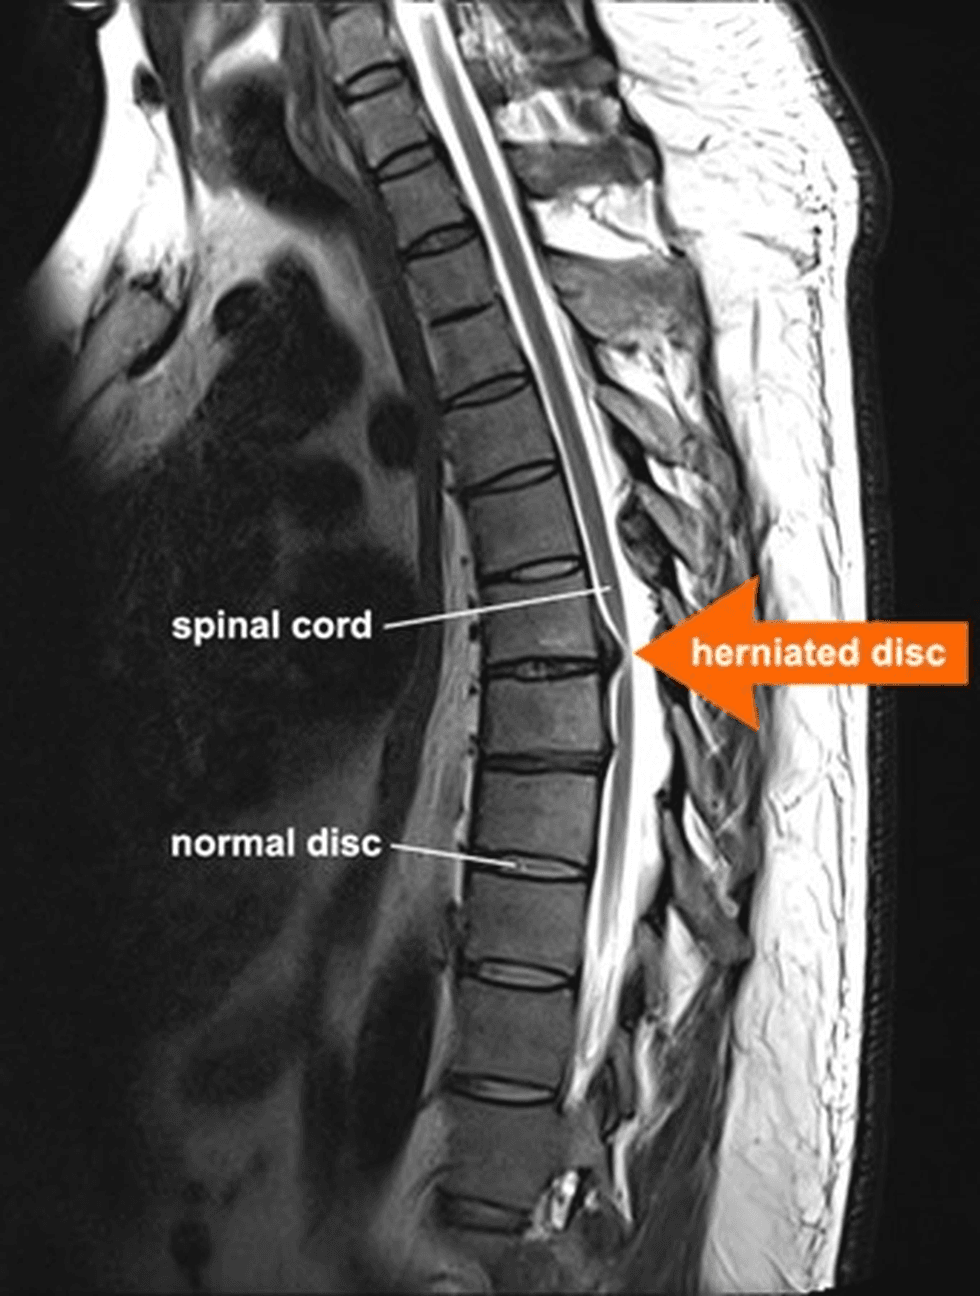

Disqet ndërvertebrore ndodhen mes rruazave të shtyllës kurrizore dhe veprojnë si amortizatorë natyralë. Ato përballojnë forcat që krijohen gjatë ecjes, uljes, ngritjes apo aktiviteteve të tjera të përditshme.

Një fakt interesant është se disku ndërvertebror nuk ka furnizim të drejtpërdrejtë me gjak. Kjo do të thotë se ai nuk ushqehet në të njëjtën mënyrë si shumë inde të tjera të trupit.

Sa herë që shtylla kurrizore lëviz, disku përjeton një cikël të vazhdueshëm kompresimi dhe dekompresimi. Ky proces ndihmon në qarkullimin e lëngjeve dhe të lëndëve ushqyese brenda diskut.